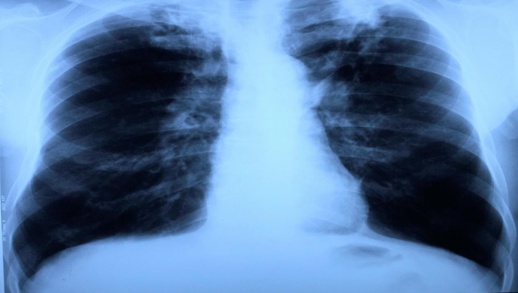

كشفت وزارة الصحة عن معطيات جديدة بخصوص مرض السل بالمغرب، حيث أكدت أن عدد الإصابات تصل أزيد من 30 ألف إصابة سنويا، مع ارتفاع نسب الكشف عن الداء إلى 88 في المائة، موضحة أن نسب الإصابة في صفوف الذكور أكثر من نسب الإصابة في وسط الإناث.

وأشارت المعطيات ذاتها إلى أن 86 في المائة من حالات داء السل تتركز في 6 جهات، و70 في المائة من الحالات المسجلة بضواحي 5 مدن كبرى، موضحة أن علاوة المغرب يسجل 217 حالة سنويا من السل المقاوم للأدوية، والذي يعد من أخطر أنواع السل في العالم.

وعن عدد الموتى جراء الإصابة بالسل، أعلن المصدر ذاته عن تراجع نسبة الوفياة بالداء بنسبة 68 في المائة.